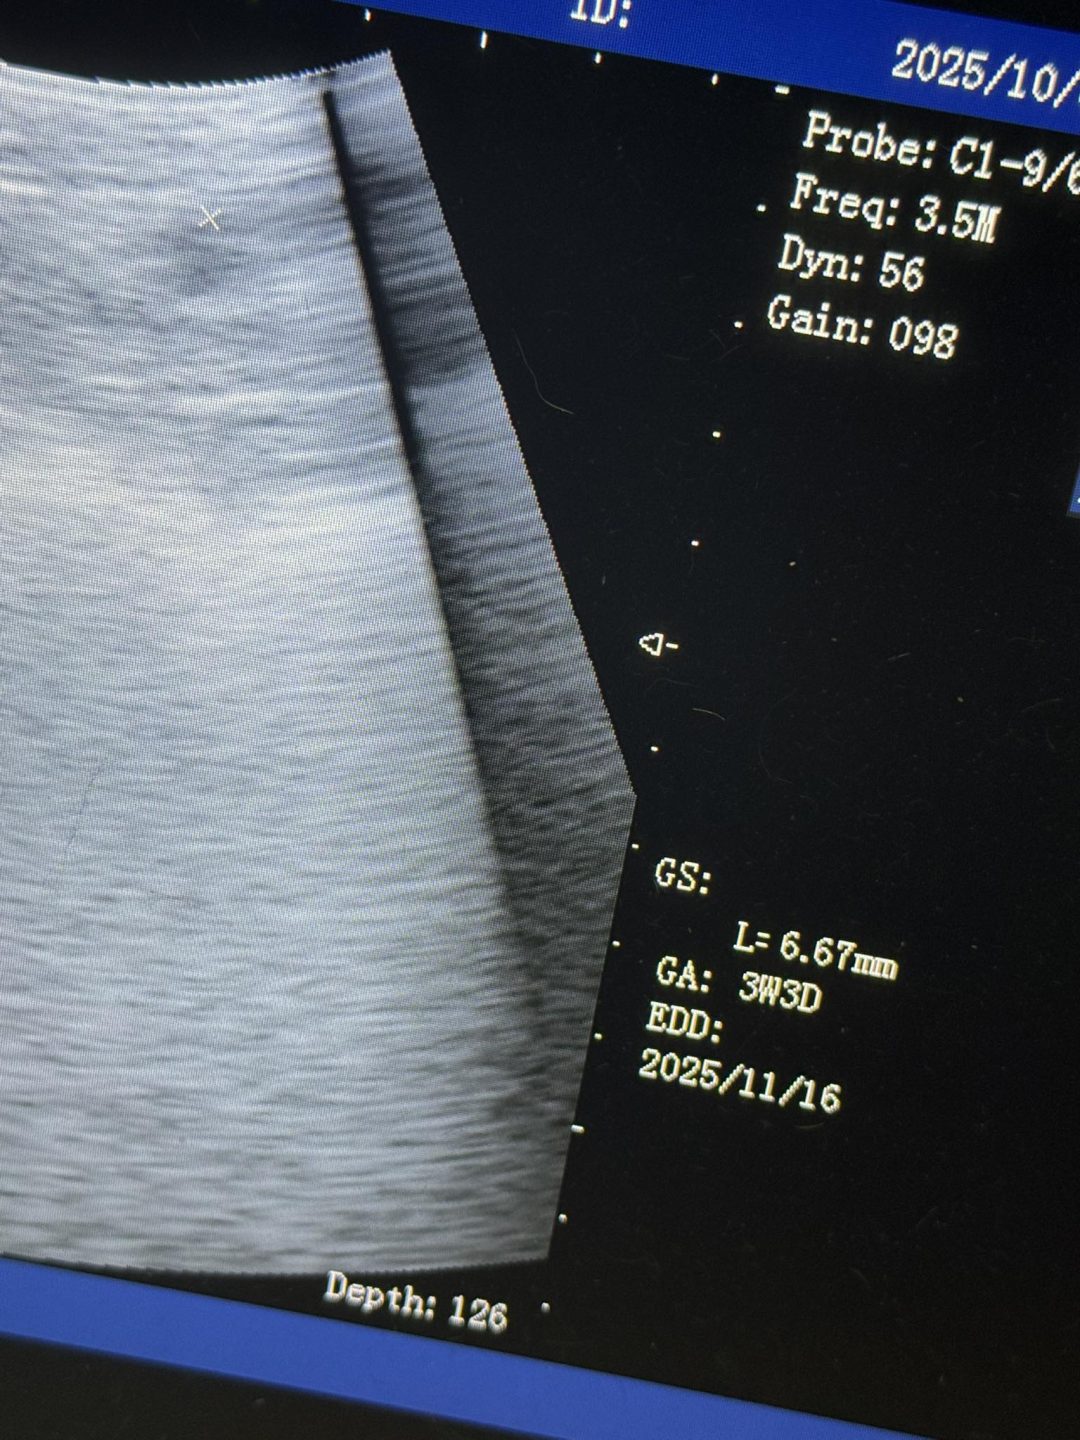

You can just see the sac and the sac measured to the correct point of how far she should be pregnant